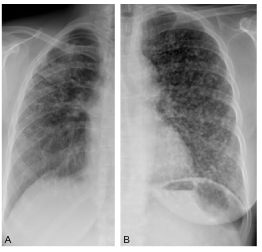

Elle montre des opacités diffuses, non systématisées, réticulaires (entrecroisement de lignes, figure 97.1A) et/ou micronodulaires (images arrondies, figure 97.1B) dont la répartition sur la hauteur du poumon est à apprécier.

Fig. 97.1. Radiographie thoracique.

Images réticulaires de l’hémithorax droit (A, sarcoïdose) et nodulaires de l’hémithorax gauche (B, miliaire métastatique).

Source : CERF, CNEBMN, 2022.